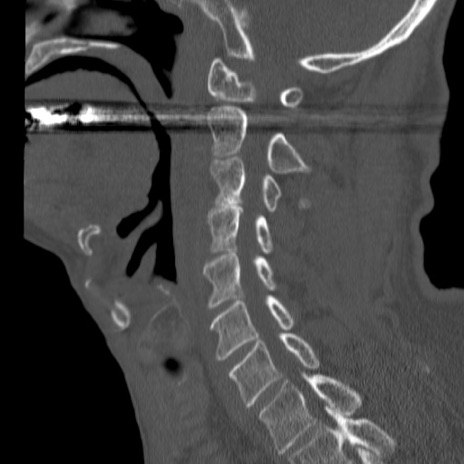

症例46 頚椎CT(矢状断像)

【症例】80歳代男性

【主訴】両側頚部〜上肢のしびれ

【現病歴】昨日、自宅内で転倒、その後より上記症状あり。意識障害なし。

【身体所見】両側上肢のallodynia(熱痛覚過敏)あり。MMTおよびDTRは正確な所見取れず。両上肢の挙上はなんとか可能。

異常所見と診断は?